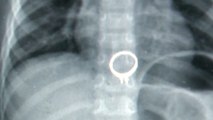

Three-year-old Chinese boy swallows mother’s diamond ring